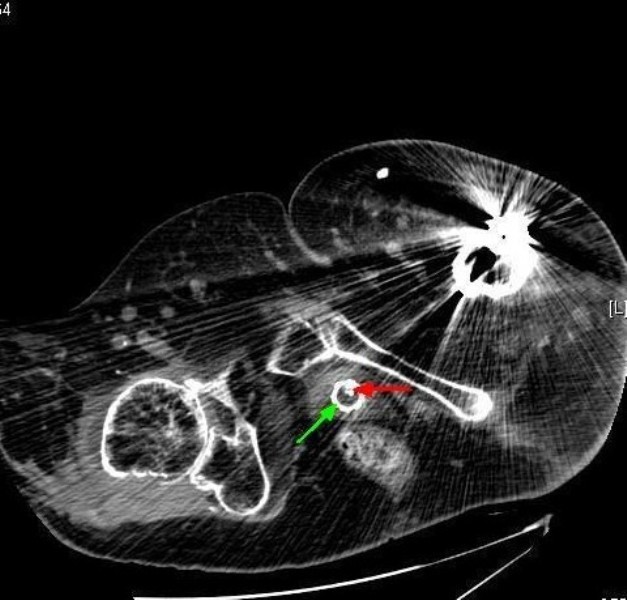

Figure 7From: Lessons we learn from review of urological procedures performed during three decades in a spinal cord injury patient: a case reportComputed tomography of pelvis (24 February 2009): axial section shows circular ring of stent located just behind symphysis pubis (green arrow); a wire is protruding into the lumen (red arrow).Back to article page